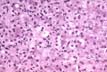

Polyploid Nuclei

Fig 64a - Presence of hepatocytes with many polyploid nuclei is another manifestation of increased liver cell renewal.Notice in this slide the nucleus of one hepatocyte being much larger than the rest.Polyploidy is the result of a mitosis that has completed the DNA replication phase but did not enter the phases of division.